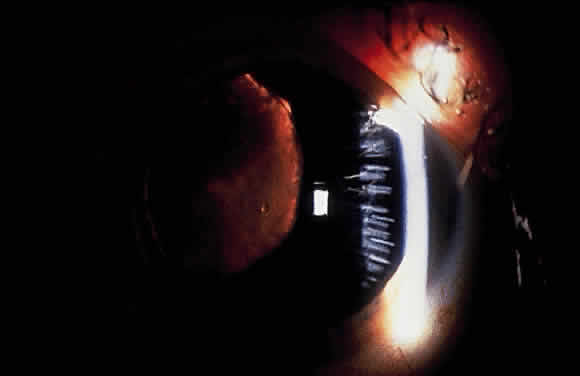

Some patients with XFS exhibit phacodonesis and subluxation of the lens, apparently resulting from degenerative changes in the zonular fibers.45–47 (Fig. 3) Spontaneous dislocation of the lens into the vitreous has been reported.48 In 1970, Bartholomew described 22 spontaneously displaced lenses in 19 patients with the disorder.45 Sixteen of the lenses were subluxated inferiorly. In these eyes, he visualized superior zonular fibers that were coated with exfoliative material and further noted that the zonular breaks generally were present at the ciliary body attachments and not at the lens, leading him to hypothesize that the main degenerative process occurred at the insertion of the zonular fibers to the basement membrane of the ciliary body epithelium. By electron microscopic examination, Schlötzer-Schrehardt and Naumann noted disruption of zonular fiber structure at the ciliary body insertion sites in eyes with XFS but also observed abnormalities at the attachments to the anterior lens capsule.46

Fig. 3. Subluxated lens in an eye with exfoliation syndrome. (Courtesy of Dr. Ronald Gross, Cullen Eye Institute, Houston, TX)